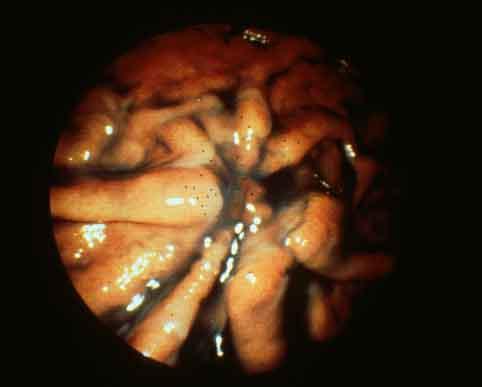

Signet ring cell carcinoma showing the characteristic findings of type 0-IIc (superficial depressed type) early gastric cancer.

Malignant epithelial tumor/Signet-ring cellcarcinoma

Type 0/IIc (IIc) Superficial depressed type

15 - 19

submucosa